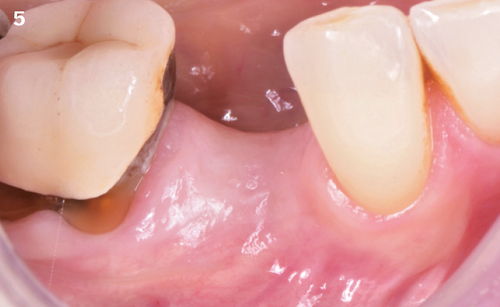

"After the extraction, I realized that the buccal wall was missing and I had to leave the membrane exposed. The regenerative potential of the site could be poor, so I decided to boost the biomaterials’ effect with polynucleotides and hyaluronic acid."

The Situation

The patient (45 years old, female, non-smoker, no previous pathologies) is referred for extraction of tooth 45 and immediate implant placement. The site showed an increased probing depth and a marked bone loss.